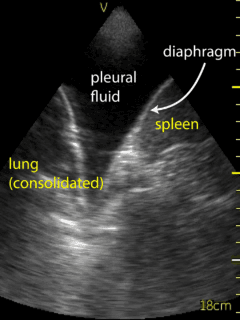

The patient’s right pleural space was assessed by the consultant Respirologist using a VScan device. A small amount of fluid in the right pleural space was noted to be gelatinous in appearance and loculated. Adjustment of the probe to the 6th intercostal space, roughly 10 cm from the spine helped to localize the largest fluid loculation in order to conduct the diagnostic thoracentesis (Figure 3, Video 3).  Following informed written consent, and lidocaine anesthesia in a sterile fashion, an angiocather was introduced guided by the ultrasound location of the largest pocket of fluid.  Approximately 70 ml of bloody fluid was collected.  The patient tolerated the procedure well without complication. Ultrasound post procedure persistence of fluid with several loculations remaining. The collected fluid was sent for routine analysis, cytology, flow cytometry, and culture.